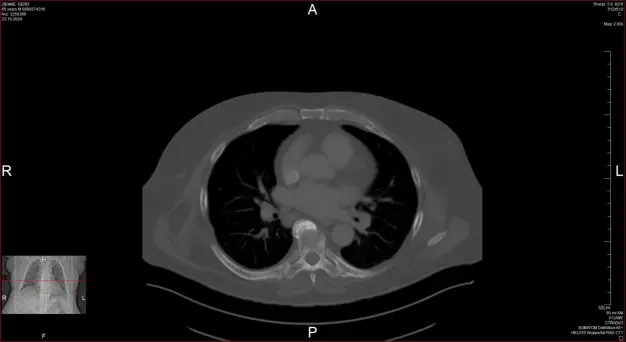

CT vom 24.07.2025

Sternum Loch